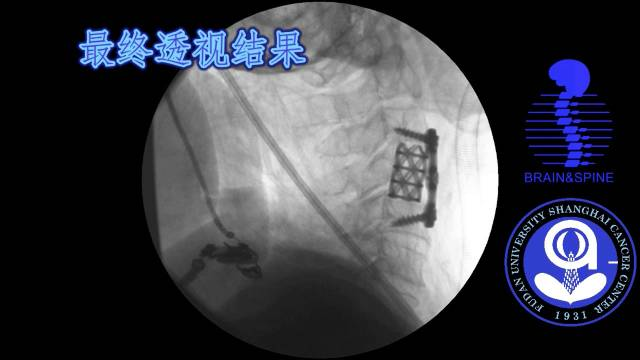

手术过程

术后情况